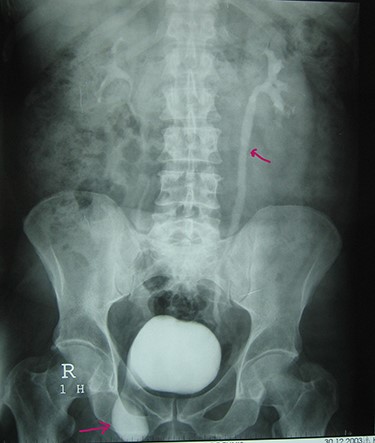

A 72-year-old man with a history of controlled diabetes and hypertension presented to our department with right inguinal swelling and intermittent lower urinary tract symptoms (LUTS) with pollakiuria, dysuria, prolonged micturition time and a sensation of a full bladder after micturition. He reported nausea, vomiting and right lower quadrant paint. The patient also reported having to manually compress the scrotum in order to empty the bladder. Physical examination revealed a slightly painful on palpation and reducible 6 cm right inguinal hernia extending into the right hemiscrotum. The body mass index of the patient was 31.4 kg/m2. His PSA was 4.3 ng/ml. On uroflowmetry, maximum flow rate (Qmax) was 13 ml/s and the voided volume was 180 cc. The uroflow curve was flat. The Bacteriological examination of urine was negative. Retrograde urethrocystography revealed right inguinal hernia containing a portion of the urinary bladder (Figs 1,2). He also had an intravenous urography in order to study the upper urinary tract and to have an idea of the renal function. This radiological exploration confirms the data of the retrograde urethrocystography and illustrates well the bladder hernia. However, a moderate left hydronephrosis with a nonobstructive pyelic calculus of 1.5 cm was observed on intravenous urography (Figs 3,4). Intraoperative findings revealed a direct right inguinal hernia with complete herniation of bladder into the scrotum. The bladder appeared healthy with no signs of injury and was restored to its normal anatomical position without resection. The hernia was repaired with a biologic mesh by the Lichtenstein technique. The patient had an uneventful postoperative course. Concerning his pyelic calculus problem, shock wave lithotripsy sessions were scheduled.

Intravenous urography: nonobstructive pyelic calculus of 1.5 cm.